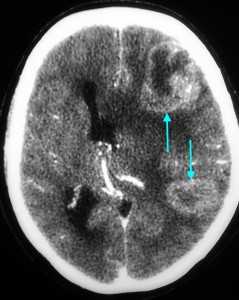

Как выглядят метастазы в головной мозг на компьютерной томографии (КТ)? Практически во всех случаях выявляется единичное (реже) либо множественные (чаще) объемные образования, которые отвечают следующим параметрам:

- Форма неправильная или сферическая

- Структура неоднородная, в центре очага может обнаруживаться область низкой плотности, обусловленная некрозом и распадом центральной части опухоли. По периферии — более плотный «ободок», который отражает активную часть опухоли, имеющую кровеносные сосуды и обладающую способностью к росту. Этот «ободок» окружен зоной низкой плотности, отражающей отек ткани мозга. Ширина данной зоны может быть различной — от нескольких мм до нескольких десятков см. Относительно однородная структура без наличия участка низкой плотности в центре и без перифокального отека. Такая структура метастаза свидетельствует о его относительной «доброкачественности»

- Отношение к прилежащим мозговым структурам. Очаги могут оказывать объемное воздействие различной степени выраженности на прилежащие отделы мозга, вызывая их смещение. Например, объемное образование в височной доле чаще всего приводит к выбуханию гиппокампа под намет мозжечка (височно-тенториальная дислокация), объемное образование мозжечка может воздействовать на мозговой ствол, приводя к его сдавлению, и т. д. Смерть при метастазах в мозг может наступить в результате сдавления мозгового ствола и нарушения дыхания и сердечной деятельности. В зависимости от локализации, вторичные очаги могут приводить к сдавлению церебральной ликворной системы, приводя к развитию окклюзионной гидроцефалии (резкому расширению центральных ликворных пространств на фоне повышения внутримозгового давления при окклюзии путей оттока ликвора из полости черепа)

- Тип роста. Метастазы могут обладать инфильтративным типом роста (расти, разрушая окружающие ткани) и экспансивным типом (расти, раздвигая окружающие ткани). В первом случае они чаще всего дают осложнения в виде кровоизлияния, то во втором обычно обуславливают возникновение дислокаций.

- Параметры контрастного усиления. Типичные вторичные опухоли в головном мозге увеличивают свою плотность в периферических отделах при внутривенном введении контраста, принимая вид «кольца», «полукольца», «спирали». Гораздо реже наблюдается равномерное контрастное усиление очага. Обычно центральная зона опухоли не усиливается, как и область перифокального отека.

Метастазы головного мозга, фото. На КТ с контрастным усилением у пожилой пациентки (в верхнем ряду слева) с жалобами на головные боли выявлены множественные объемные образования в левом полушарии мозга, интенсивно накапливающие контрастное вещество. Образования имеют характерную форму в виде «кольца». На изображениях в нижнем ряду и вверху справа определяются множественные очаги в головном мозге: отчетливо видны округлые образования с более плотным «ободком» по периферии, располагающиеся в левой теменной доле.